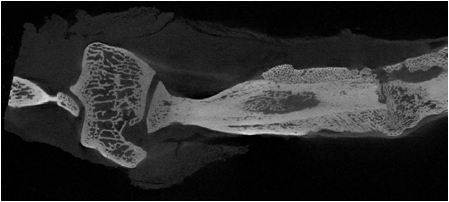

Inoltre, nel Settore di Istomorfometria, Microarchitettura Biomateriali Osso vengono eseguite valutazioni istomorfometriche tridimensionali su morfologia e colonizzazione cellulare di scaffolds, tessuti biologici mineralizzati, vascolarizzazione di organi e tessuti utilizzando una microtomografia computerizzata di ultima generazione (SkyScan 1172).

Vengono effettuate analisi per caratterizzare biomateriali, scaffold e dispositivi in fase pre-impianto che all’espianto. In particolare:

- analisi di biomateriali prima dell’impianto per valutarne porosità o caratteristiche meccaniche;

- analisi di impianti metallici, utilizzati di frequente sia in ortopedia che in odontoiatria, in cui è di primaria importanza lo studio della crescita ossea attraverso la rigenerazione e l’osteointegrazione;

- analisi di impianti polimerici o ceramici per la rigenerazione di difetti e perdite di sostanze ossee;

- studio della morfologia dell’osso, estremamente importante perché numerose patologie ne alterano la microarchitettura (osteoporosi e altre patologie o terapie che influenzano il tessuto osseo). Inoltre, dopo l’impianto di un biomateriale è importante non solo valutare quantitativamente la crescita ossea, ma anche la qualità dell’osso rigenerato. Oltre alle analisi istomorfometriche 3D, vengono creati, partendo dalle sezioni micro-CT, modelli tridimensionali virtuali che forniscono visualizzazioni realistiche del campione di grande utilità anche per comprenderne appieno le strutture.

I modelli possono venire utilizzati per creare filmati dell’oggetto analizzato in movimento o come base per prototipi in ingegneria tessutale.